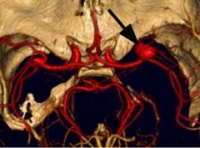

2.因颅内动脉瘤多位于颅底部WiLLis动脉环,直径小于1.0C的动脉瘤,CT不易查出。直径大于1.0cm,注射对比剂后,CT扫描可检出。MRI忧于CT,动脉瘤内可见流空。MRA可提示不同部位动脉瘤,常用于颅内动脉瘤筛选。三维CT(3D-CT)从不同角度了解动脉瘤与载瘤动脉的关系,为手术夹闭动脉瘤决策提供更多的资料。

(1)以出血为首发征像时,临床怀疑动脉瘤而行血管成像(DSA、CTA、MRA)可证实动脉瘤的存在,一般无需鉴别,但应注意假阳性和假阴性的存在。假阳性如颈内动脉起始部、后交通动脉起始部漏斗样增粗如正常现象,血管转折处在MRA上易误为异常,两段狭窄间正常管腔易误为动脉瘤等。假阴性如动脉瘤破裂或痉挛导致造影时不能显示等。这方面CTA较DSA和MRA有明显优势,它可以对单枝血管进行曲面重建并旋转观察,有利于分析动脉壁的结构是否正常,有利于发现无造影剂充盈的瘤体等。